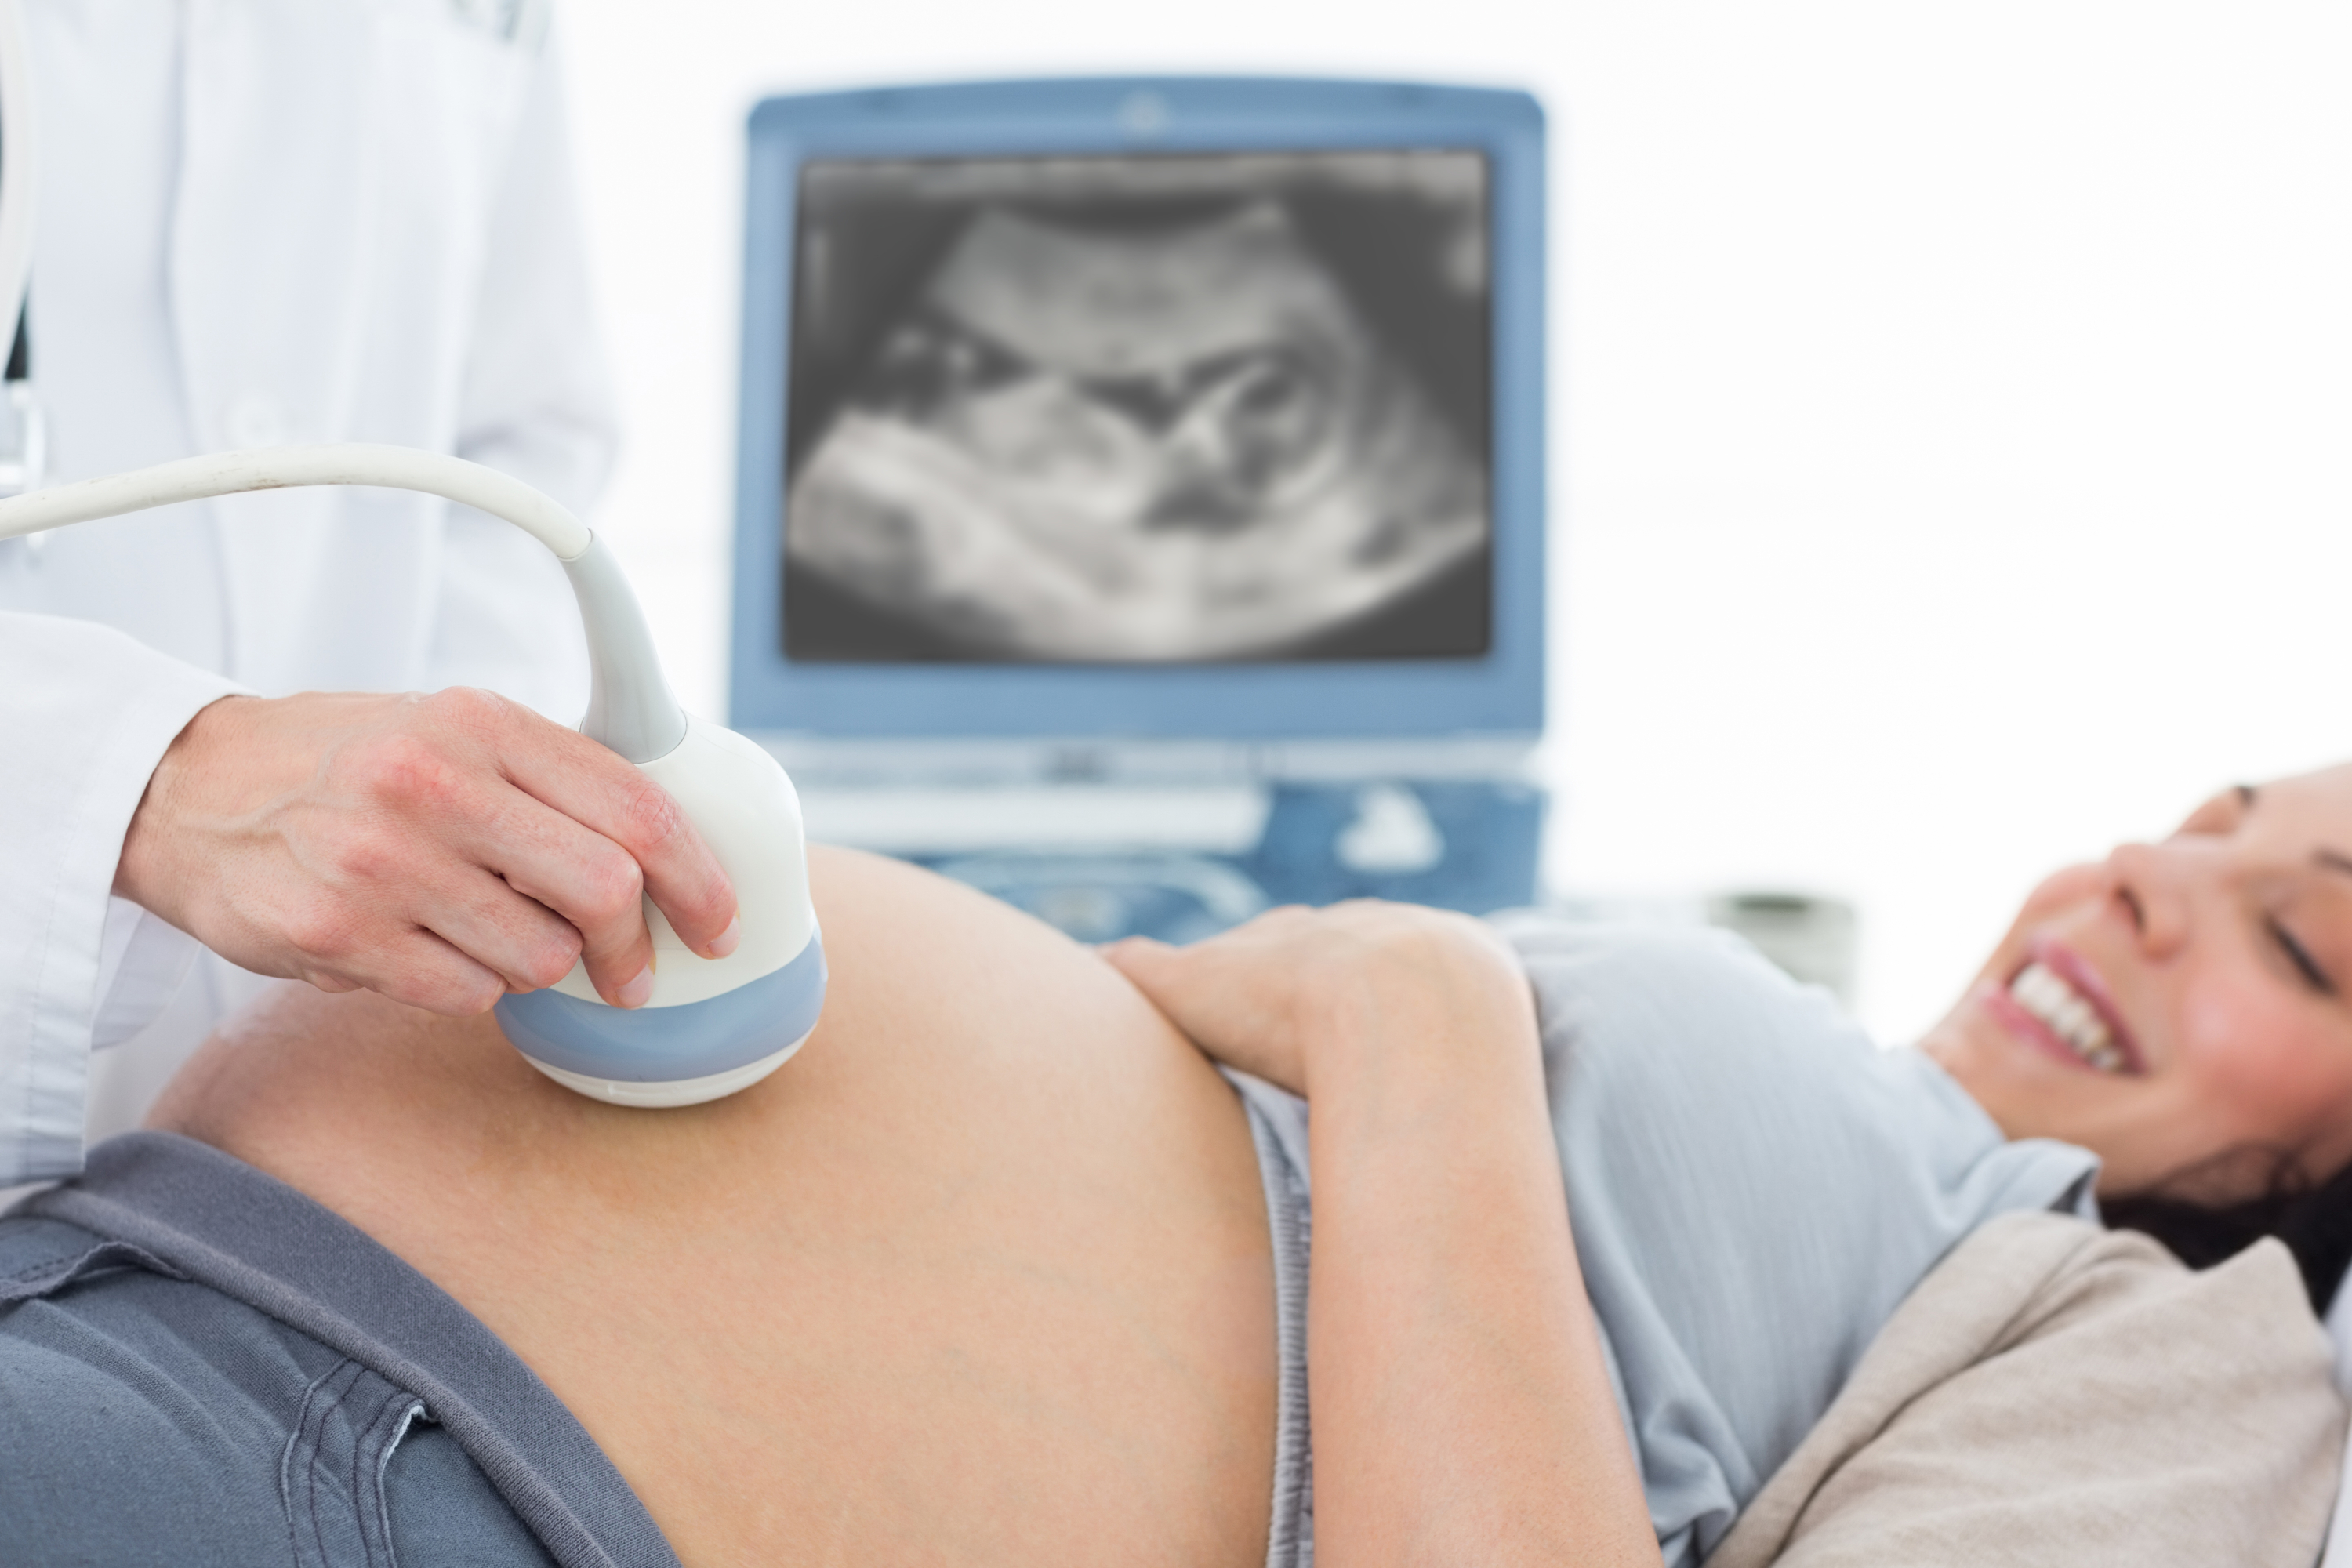

¿Cuándo se recomienda un seguimiento especializado?

Un seguimiento especializado solo se recomienda en casos donde el foco ecogénico se acompaña de otras anomalías en la ecografía que puedan indicar un mayor riesgo de problemas cromosómicos. En tales situaciones, el médico podría sugerir pruebas adicionales, como una ecocardiografía fetal o pruebas genéticas, para evaluar con mayor precisión la salud del feto y descartar cualquier complicación.

Como indica nuestra experta, Carolina Paladino, "lo primero de que se debe hacer es realizar es un escaner detallado fetal, para valorar la presencia de otros marcadores blandos, que serían pequeñas variaciones de la normalidad, como el intestino hiperecogénico o una pielectasia, por nombrar algunas. Si el hallazgo es único, no solemos realizar más estudios".

La ginecóloga también indica, que si por el contrario, además del foco hallamos otra anomalía, se recomienda realizar estudios para descartar anomalías cromosómicas, como puede ser una amniocentesis. De hecho, el ecocardiograma fetal no estaría indicado, salvo que se sospeche de una cardiopatía asociada.